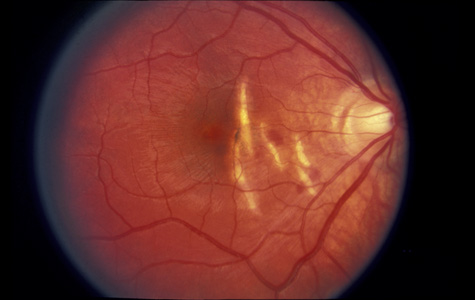

Courville24,25 introduced the concept of coup and contrecoup injury to explain brain damage caused by blunt trauma to the head. Coup refers to local trauma at the site of impact. Contrecoup refers to injuries at the opposite side of the skull caused by shock waves that traverse the brain. Foci of brain damage are found along the path of the shock waves, especially at interfaces of tissues of different density. The greatest difference in density is between the brain and the skull, and it is here that the most severe damage occurs. Wolter later used these concepts to explain eye injuries.26 Examples of coup injuries are corneal abrasions, subconjunctival hemorrhages, choroidal hemorrhages, and retinal necrosis (Fig. 1). The best example of a contrecoup injury is commotio retinae (Fig. 2). These injuries are discussed later in this chapter.

Fig. 1. A: Coup injury. At the site of impact of a stick, subretinal and vitreous hemorrhage are present. B: Three months later, most of the hemorrhage has cleared, revealing choroidal and pigment epithelial necrosis.